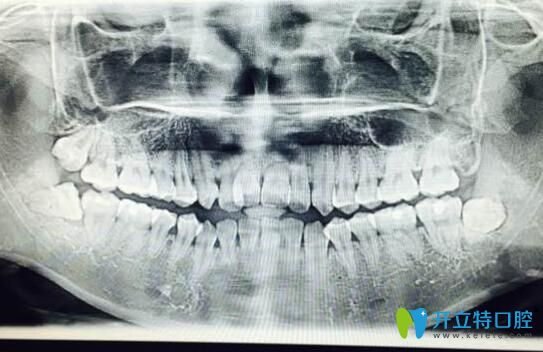

案例一:90后自述門牙牙根短做矯正感受:

首先我的門牙牙根很短,兩個(gè)醫(yī)生拒絕給我矯正的,但是我整牙欲望很強(qiáng)烈,冒著風(fēng)險(xiǎn)做了,也不知道以后會(huì)出現(xiàn)什么問(wèn)題,門牙是否真的掉了,到時(shí)候再說(shuō)吧,問(wèn)題出了再去解決…

90后自述門牙牙根短做矯正感受

?牙齒矯正2個(gè)月:?感覺牙齒變化速度比較慢,目前牙齒還沒又松動(dòng)神馬的感覺。